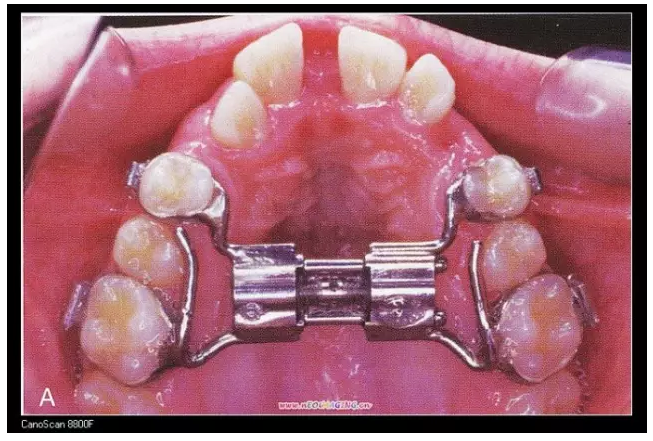

三、擴(kuò)弓器

很多牙列不齊常伴隨牙弓過窄,所以擴(kuò)弓器是正畸醫(yī)生的好伙伴,它可以以多種形態(tài)和您見面。